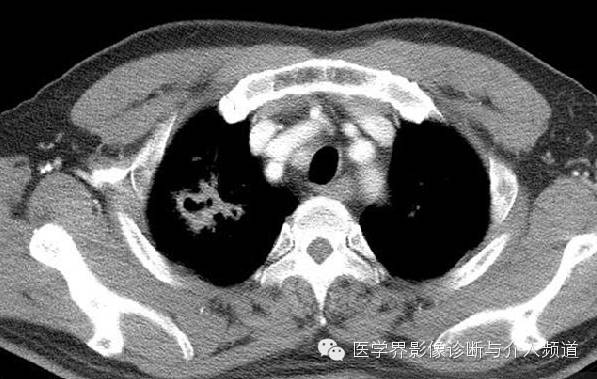

治疗后

CT显示右肺上叶实性团块病灶内不规则空洞形成,周围可见GGO,右侧胸腔少量积液。患者外周血嗜酸性粒细胞增多和Pw抗体阳性。治疗后X线平片显示右上肺结节影缩小。治疗前X线片显示病灶位于右肺上野,右侧肋膈角变钝。此外,X线平片示主支气管节段性偏心性狭窄,这是由于胸内甲状腺肿外在压迫所造成。